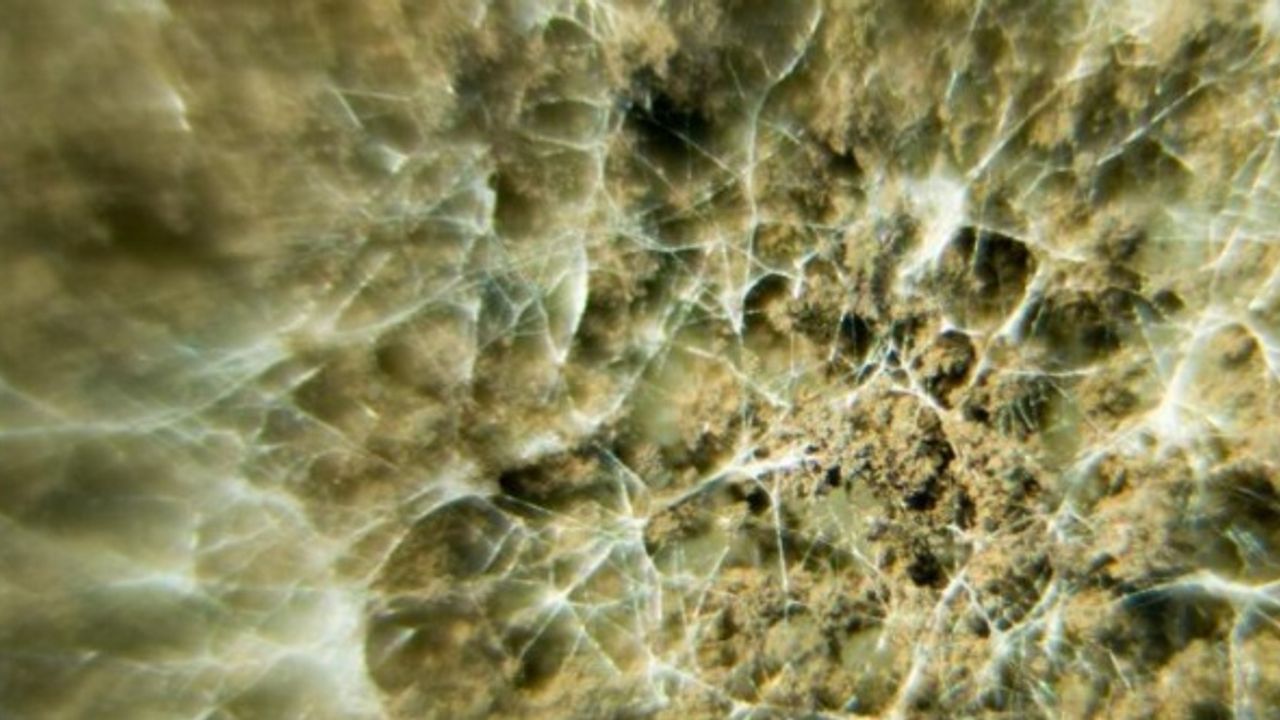

Prof. Dr. Bülent Ertuğrul kara mantarı, “Aslında tam doğru bir adlandırma olmamakla birlikte mantarın yapmış olduğu infeksiyona bağlı olarak doku renginin siyahlaşması nedeniyle bu şekilde adlandırılan hastalık etkeni Mucormycoses denilen bir mantar türüdür” diye tanımlıyor.

Bu mantar türünün doğal yaşamda bolca bulunduğundan ve günlük yaşamda sürekli karşımıza çıktığından bahseden Ertuğrul, “Örneğin bir meyveyi buzdolabı dışında bir yerde beklettiğimizde bir süre sonra siyah bir küf kaplandığını görürüz. İşte bu küf aslında bu hastalığın etkeni olan mantar türüdür” diyor.